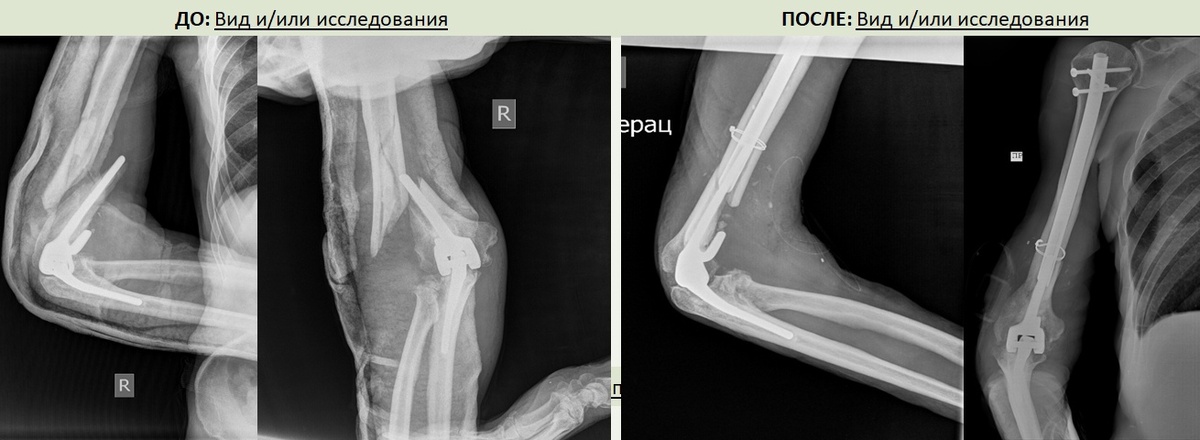

рентгенограмма ДО и ПОСЛЕ

При падении пациент сломал плечевую кость в области эндопротеза. Травма отягощалась повреждением лучевого нерва, который был защемлен между отломками костей плеча. Движений и чувствительности в руке не было.

Существующие методы – чрескостный остеосинтез по Илизарову и накостный остеосинтез не позволили бы достичь поставленных задач. А учитывая, что поврежденный сегмент крайне сложный, с точки зрения интраоперационных рисков: близко сосуды и нервы, вариант применения погружного остеосинтеза тоже рассматривался с большим опасением.

Второй этап операции выполняли травматологи-ортопеды: руководитель Клиники, д.м.н. Алексей Гринь совместно с заведующим травматолого-ортопедическим отделением №2, к.м.н. Евгением Дарвиным. Ими был установлен штифт, скрепляющий кость и эндопротез локтевого сустава.